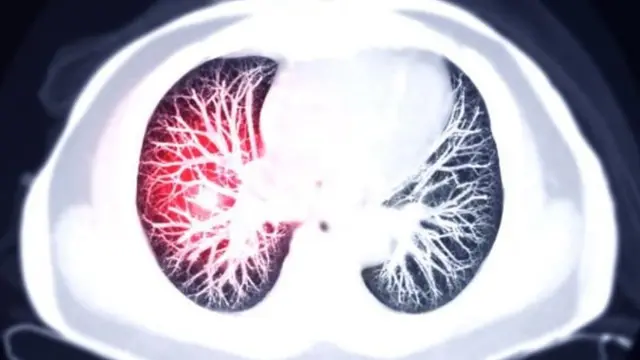

इन थक्कों के बनने की वजह से फ़ेफ़ड़ों में गंभीर सूजन पैदा होती है. कोरोना वायरस से शिकार मरीज का शरीर सामान्य प्रतिक्रिया के तौर पर फ़ेफ़ड़ों में सूजन पैदा करता है.

डॉक्टरों को और भी कई चौंकाने वाली चीजों का पता चला. मसलन, कुछ मरीजों के फ़ेफ़ड़ों में सैकड़ों की संख्या में माइक्रो-क्लॉट भी पाए गए थे.

वह बताते हैं, "मेरे फ़ेफ़ड़ों की स्क्रीनिंग हुई और इससे पता चला कि मेरे फ़ेफ़ड़ों में खून के थक्के जम गए हैं. मुझे बताया गया कि यह बेहद खतरनाक है."

खून में बदलाव फ़ेफ़ड़ों में गंभीर सूजन पैदा हो सकती है. वायरस का शिकार होने के बाद यह शरीर की प्राकृतिक प्रतिक्रिया होती है.